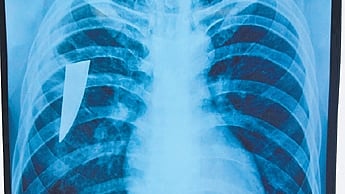

A team of doctors at CTVS department in MKCG medical college and hospital removed a piece of a knife stuck in the chest of a youth since last 3 years.  (Photo | Express)

Twenty-two-year-old Santosh Das of Kabisuryanagar was admitted to the CTVS department on April 19 due to chest pain and blood in his cough. Subsequently, an X-ray detected a piece of a knife in his right side chest. On being questioned, Santosh said that while working in Bengaluru in 2022, he was stabbed on the left side of his neck by a local during a brawl. He was admitted to a hospital for treatment. However, the piece of knife was not detected and he returned to his native after recovery.

CT scan and bronchoscopy report showed the knife piece stuck in his chest and a surgery was conducted by head of the CTVS department Prof Sarada Dash. “The broken knife piece of 8 cm was retrieved from the right side lung and the patient is stable and undergoing treatment in ICU of CTVS department,” said Prof Dash.